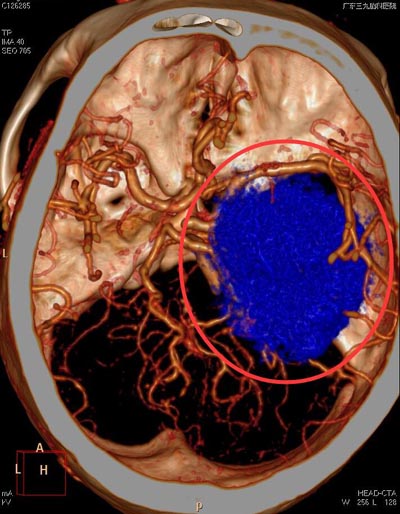

广东三九脑科医院头颅MR检查提示:鞍结节偏右侧占位性病变,大小约为51mm×60mm×48mm,考虑为脑膜瘤可能性大;头颅CTA检查提示:右侧颞部占位性病变,其内血管丰富(颈外动脉系统供血可能)。

▲术前CTA